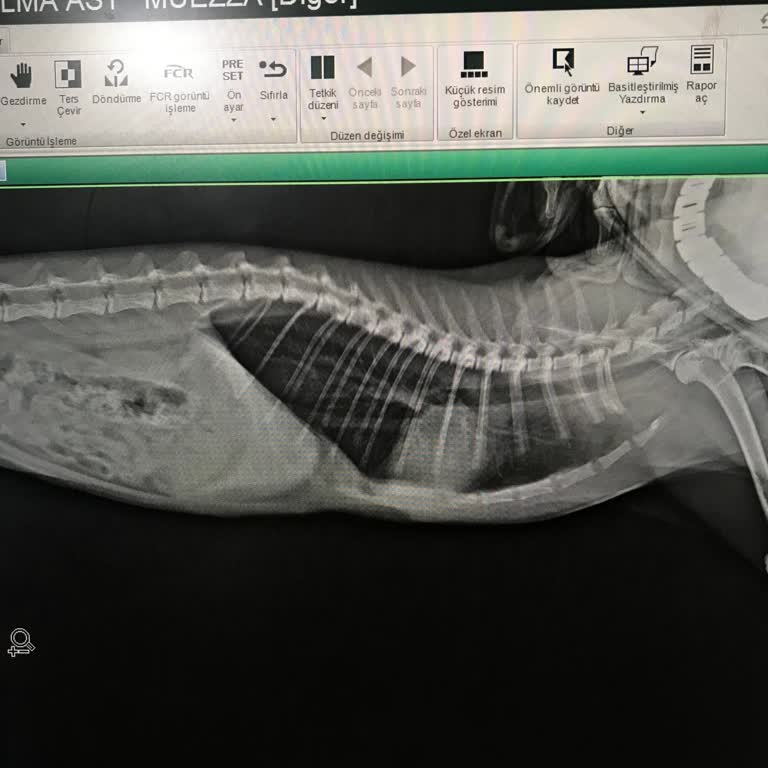

Yaklaşık iki hafta önce kedimi kusma, halsizlik ve yemek yememe şikayetleriyle Universal Fatih Hayvan Hastanesi Avcılar şubesine götürdüm. Muayene sonrasında serum ve antibiyotik tedavisi uygulandı, röntgen çekildi ve bana kedimin ciğerlerinde problem olduğu söylendi. Bu süreçte kedimin durumunun ci...